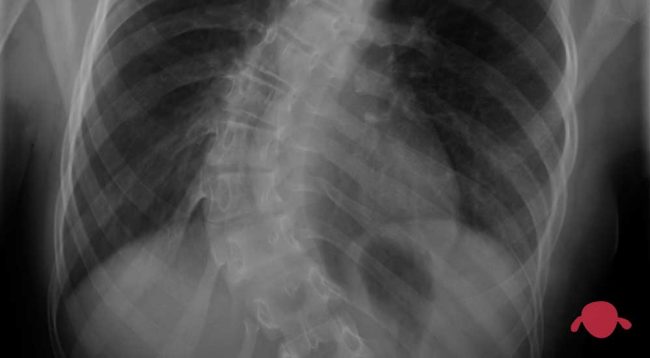

Escoliosis

Ni miedo ni vergüenza, tiene una mala fama creo que inmerecida. Como muchas otras cosas las hay malas y de las que “da igual” La escoliosis es una espalda torcida… sí, vale. Pero debe de haber algo más detrás de todo esto cuando hay traumatólogos que se dedican exclusivamente a esto. Para la escoliosis hablamos…